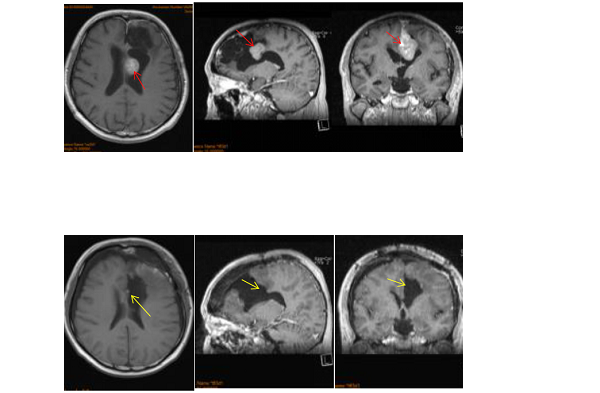

今年50岁的赵先生,确诊为多发脑膜瘤,经历了国内专家的手术切除及伽马刀治疗无果后,毅然奔赴德国接受INC国际神经外科医生集团旗下组织国际神经外科顾问团(WANG)的德国INI神经外科教授、国际神经外科联合会(WFNS)教育委员会主席巴特朗菲教授手术,目前,赵先生多发脑膜瘤术后5年,身体康复良好,没有复发转移情况。

具体手术过程:取患者仰卧位、前额部冠状切口、左侧为主。右侧额骨骨瓣过矢状窦,完全暴露矢状窦前1/3,及部分右侧额部硬脑膜。完全切除全部肿瘤,扩大切除左额硬脑膜,到达正常厚度硬脑膜为止。全切前段大脑镰,切除前1/3上矢状窦及下矢状窦。受累颅骨的内板以磨钻磨除后复位。手术实现脑膜瘤Simpson 0级切除。

术后MRI影像:左额凸面、及前段大脑镰多发脑膜瘤被全部切除;前 1/3 矢状窦被切除;前段大脑镰被切除;左额硬脑膜被大部分切除,无硬脑膜强化表现。左额术后侧脑室额角穿通。

术后情况:正常,术后ICU观察一天,术后二天下床进行康复锻炼。神经功能无任何异常,术后13天步行出院。